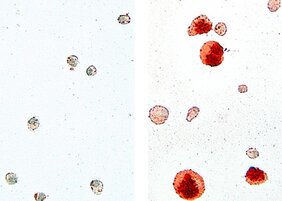

„Wir haben Alveolarmakrophagen von gesunden Mäusen und solchen, denen das Gen für C/EBPb fehlt, isoliert und in vitro-Tests sowie diverse Genom- und Transkriptomanalysen durchgeführt“, erklärt Erstautorin Dr. Dorothea Dörr. Konkret hat die Forscherin die biologischen und molekularbiologischen Eigenschaften der Alveolarmakrophagen untersucht. Sprich: wie gut sie in der Lage sind, Lipide aufzunehmen und zu verstoffwechseln. Während die Makrophagen gesunder Mäuse ordentlich ihre Arbeit verrichteten, nahmen die der genveränderten Mäuse zwar sehr viel Lipid auf und speicherten es – konnten es aber nicht mehr verdauen. Die Fresszellen quollen schaumartig auf, gingen bald zugrunde und die Lipide lagerten sich vermehrt ab. Genauso, wie Mediziner*innen es von der Lungenkrankheit PAP kennen. Außerdem konnten sich die defekten Makrophagen kaum noch vermehren.